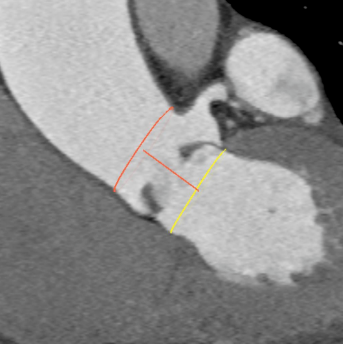

为确保手术过程万无一失,手术后患者能尽快恢复,团队全体成员反复沟通、讨论,应用医用软件分析出多方位参数,并制定各种风险的应急处理方案。

全麻后,成功穿刺右股动脉,通过穿刺点输送系统将瓣膜输送至病变的主动脉瓣处,经过严密地心电监护、心脏食道超声引导,手术团队在心室快速起搏下,使得收缩压降到 60 mmHg、脉压差小于 10 mmHg,此时释放人工生物瓣膜取代自身病变的瓣膜,食道超声检查无瓣周漏,人工瓣膜工作正常,手术完美结束。